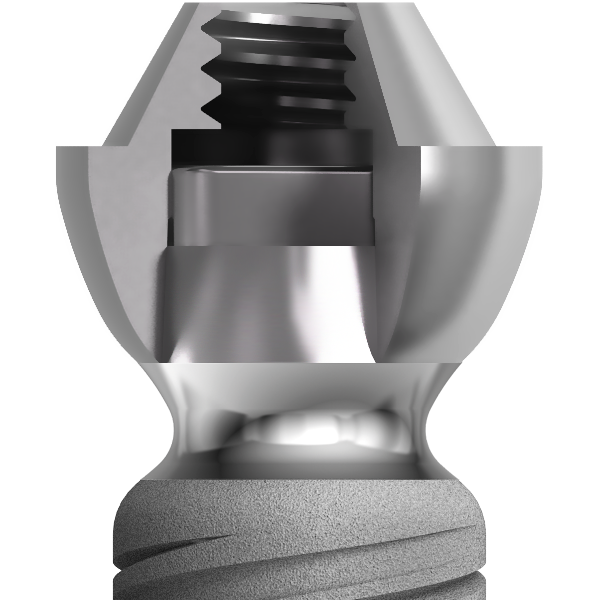

Sur le plan parodontal, la gestion du profil d’émergence a été revisitée de façon à favoriser le réaménagement d’un joint muqueux épais de première intention qui a vocation à jouer le rôle de barrière naturelle.

Le positionnement vertical de l’implant est légèrement modulable selon le biotype parodontal. L’interface prothétique est décalée au dessus du joint muqueux ; le risque de contamination iatrogène lors des phases de restauration prothétique est réduit.